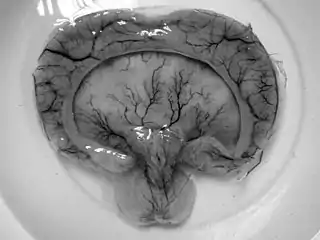

![]() Holoprosencefalia alobar, producto de una madre de 19 años en Tailandia con diabetes gestacional.[1] | ||

- Holoprosencefalia alobar es el tipo más grave, en la cual el cerebro no logra separarse y se asocia generalmente a anomalías faciales severas (fusión de los ojos, anomalías del tabique nasal.)[4]